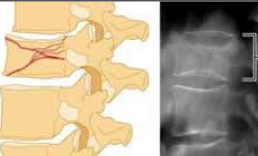

Compression fracture

common in middle/older age